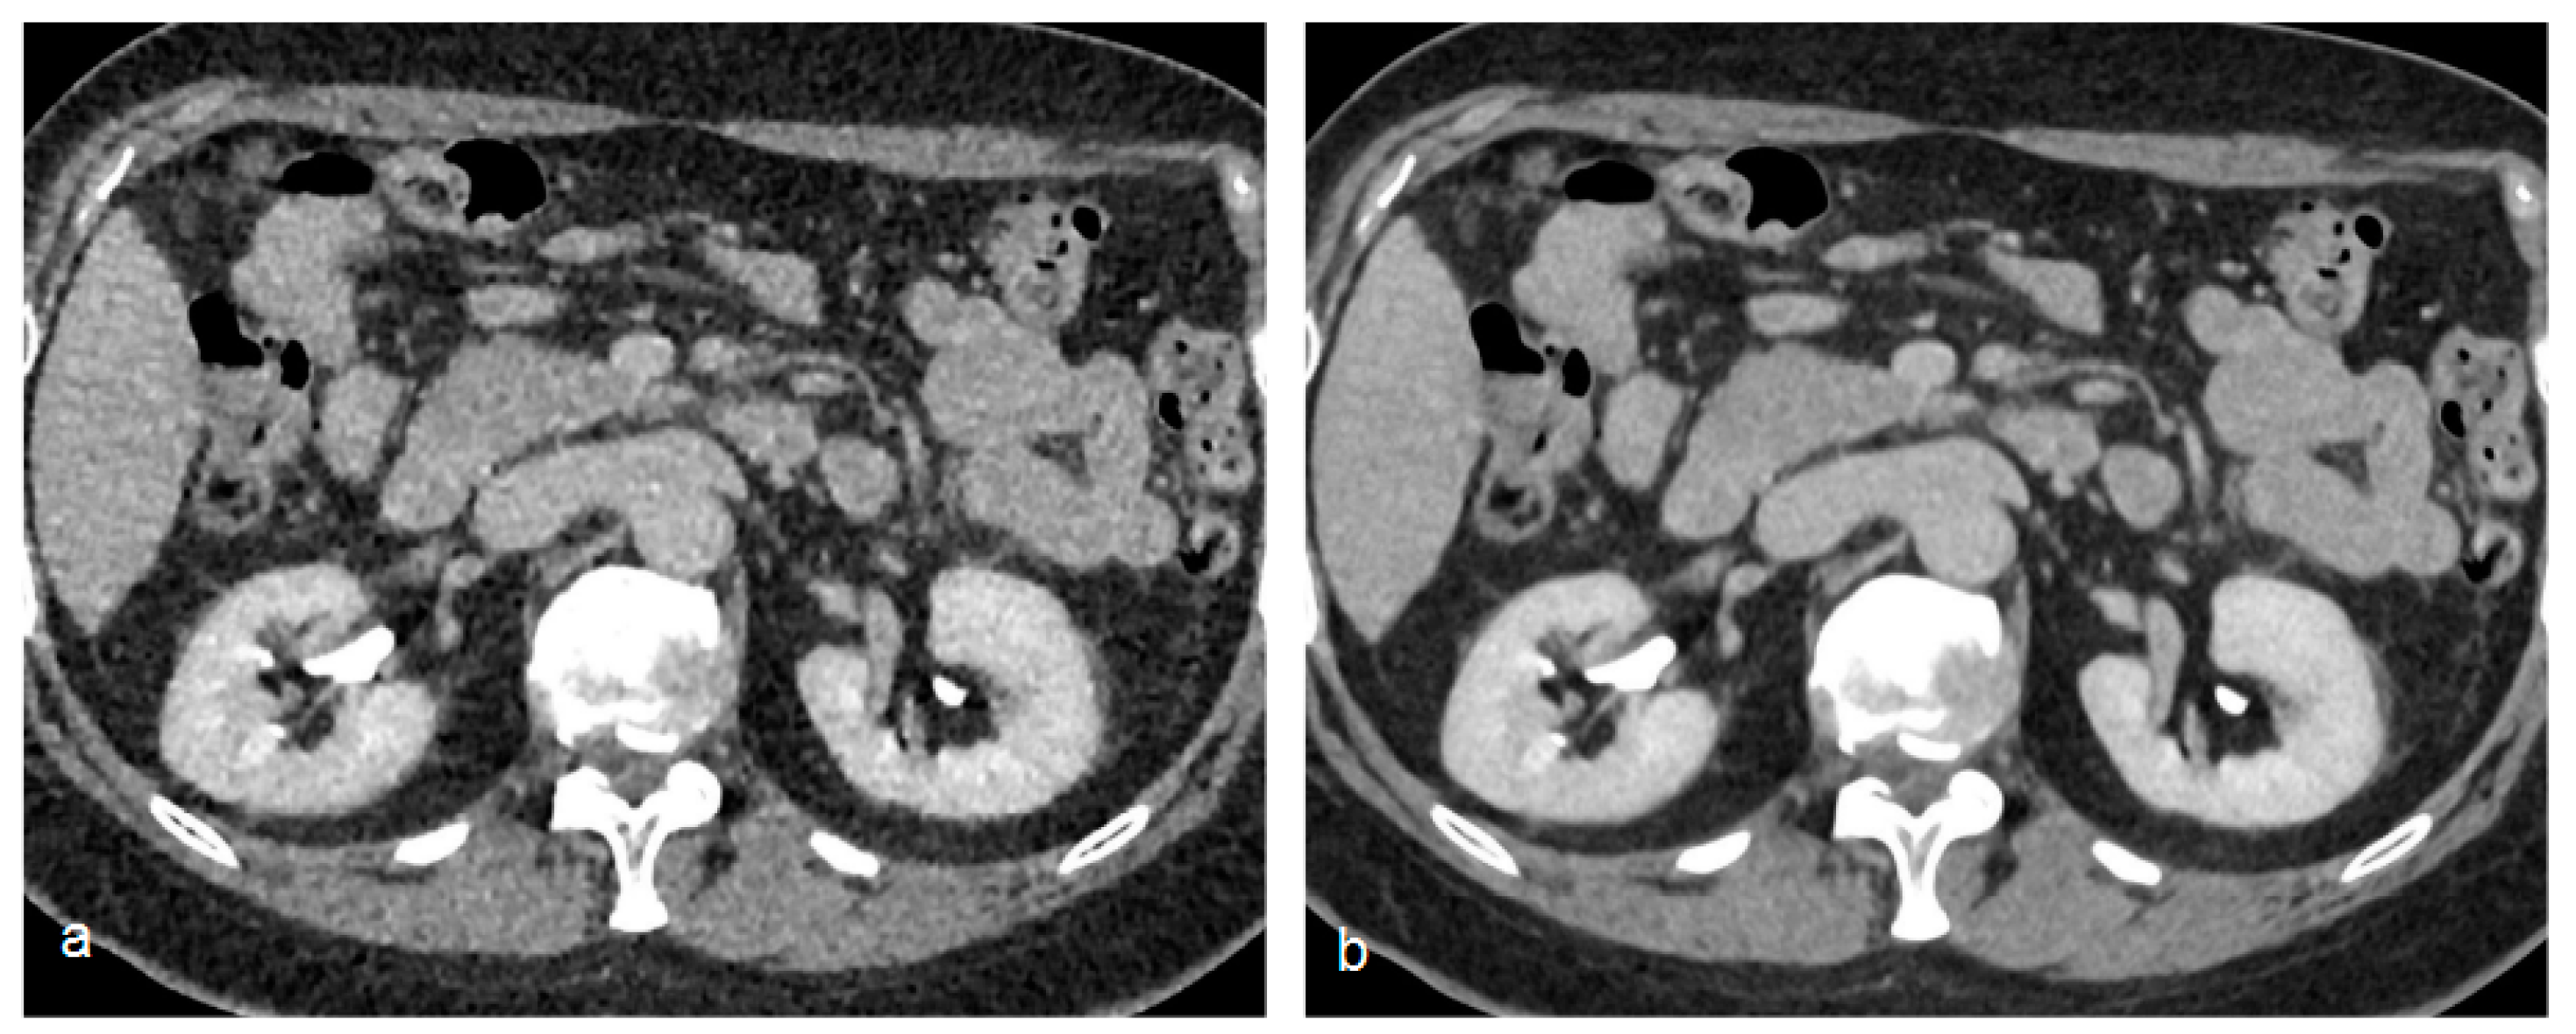

Phantom studies have demonstrated the ability of these new reconstruction algorithms both in lowering image noise and in improving spatial resolution with no increases in noise levels [45] (Figure 6).

Figure 6.

Comparison of a standard filtered back projection reconstruction (a) of an excretory phase with an artificial intelligence-based reconstruction algorithm (b) (AiCE—Advanced intelligent Clear-IQ Engine, Canon Medical Solutions). Note the significant noise reduction of the artificial intelligence-based reconstruction (b).